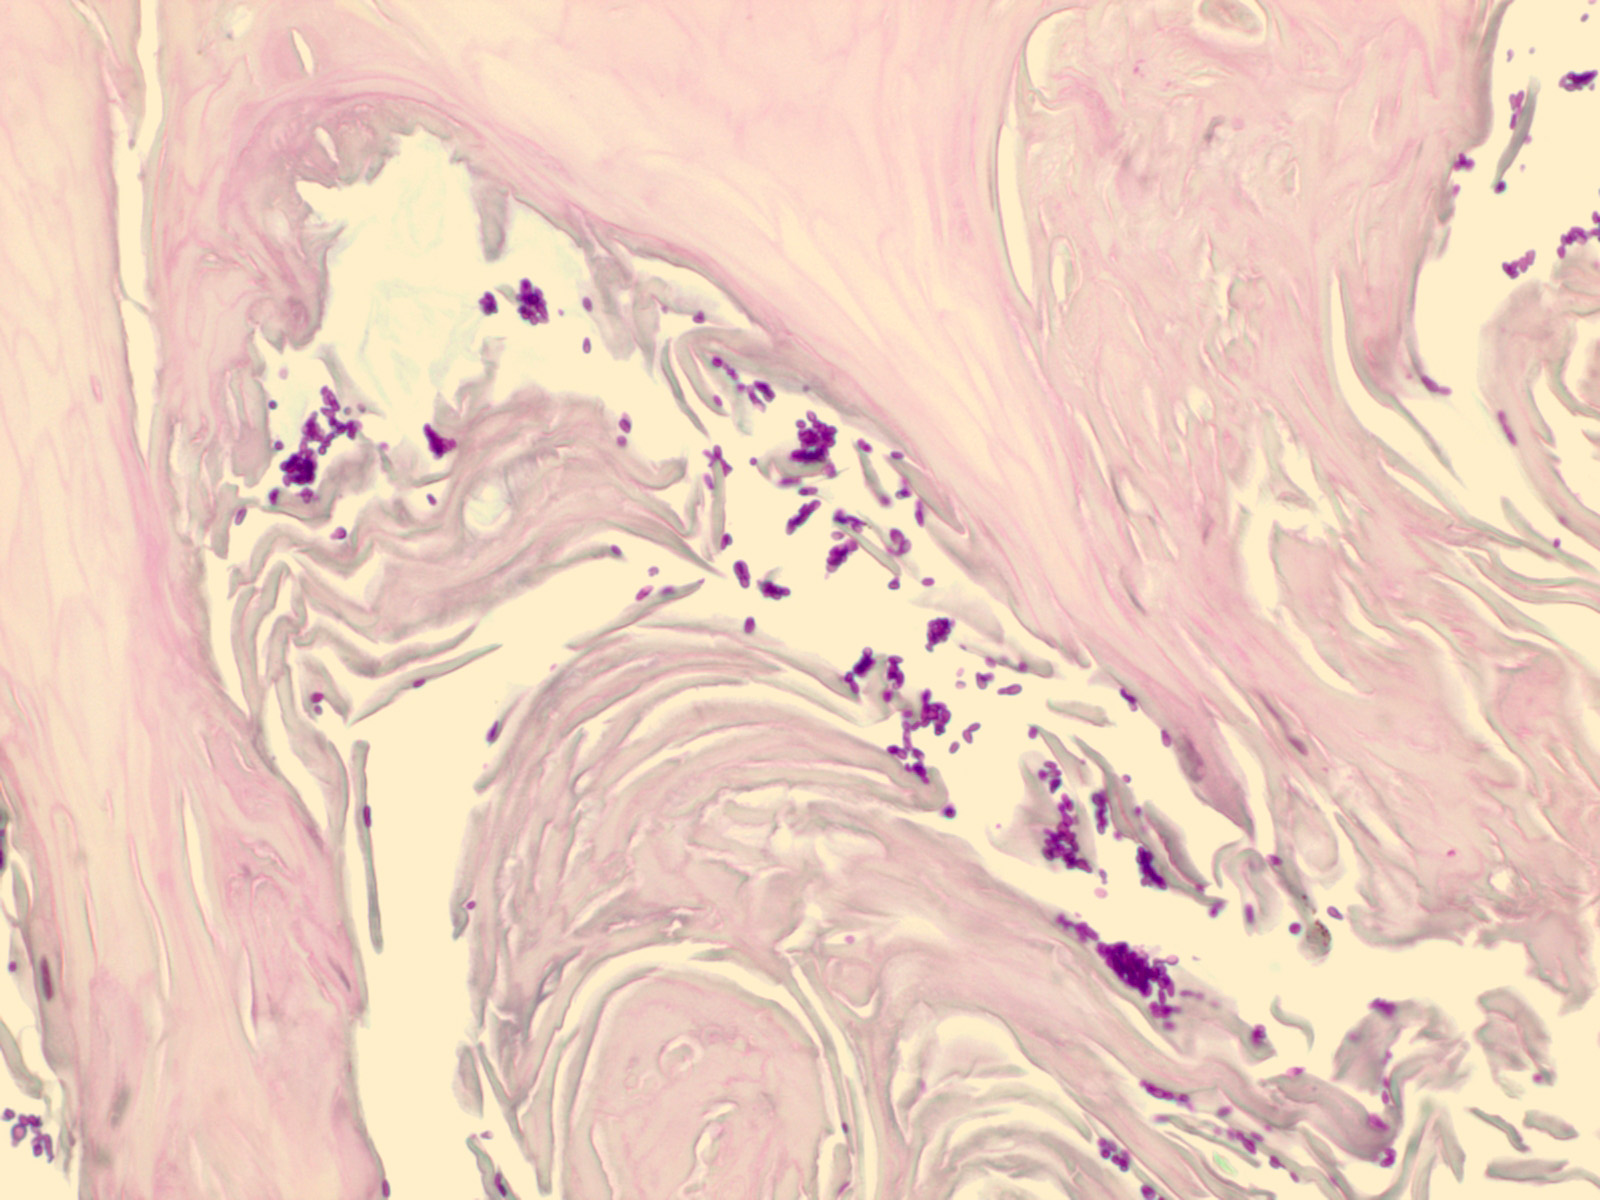

Candida onychomycosis =اصابة ظفرية بالمبيضات البيض